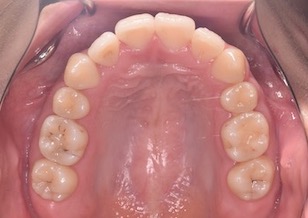

矯正後

After Ⅰ

マルチブラケット装置を装着し、左側上下顎第1大臼歯部にクロスエラスティックス(患者さん自身で付け外しのできる輪ゴム)を装着していただき大臼歯部の交叉咬合の改善を行いました。上顎左右第1小臼歯2本と下顎の左側側切歯の合計3本を便宜抜歯して歯列の整直と咬合の確立を行いました。また治療上の工夫としてIPR(エナメルストリッピング)を数カ所において行いました。

その結果、上下顎の歯並びは整直されともにキレイな歯並びとなりました。左側第1大臼歯部の交叉咬合ならびに側切歯部の反対咬合は改善され、全てのエリアで正常な咬み合わせになりました。